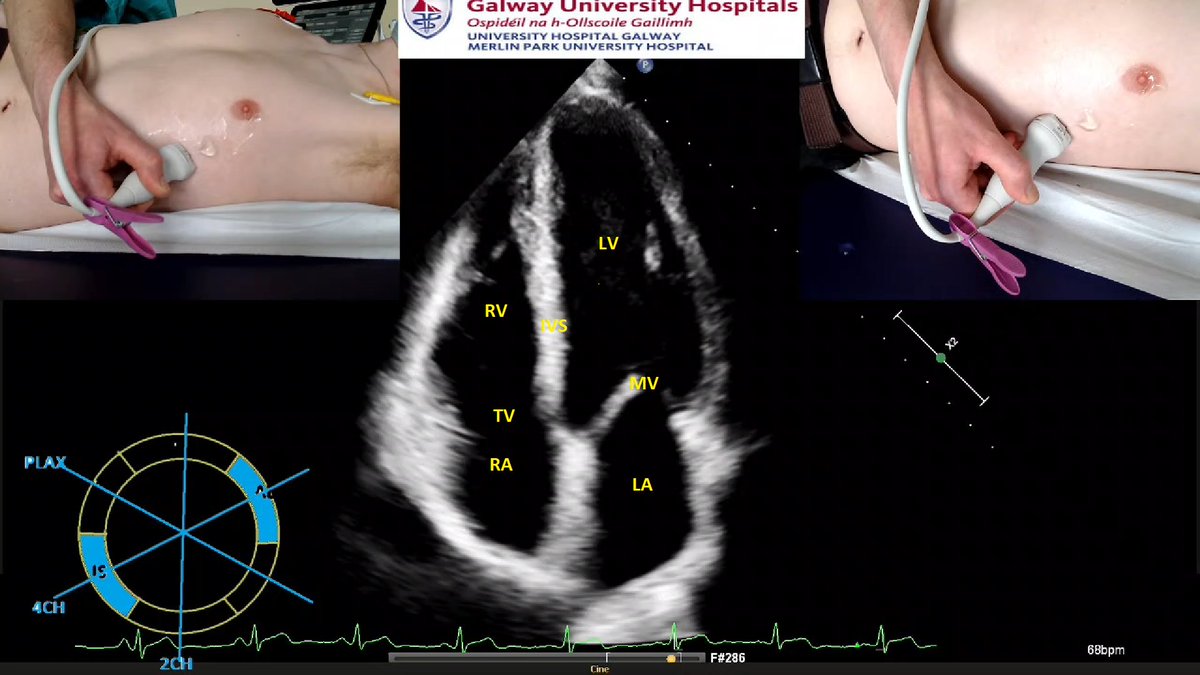

The Apical 4-Chamber

What are we looking at?

LV assessment

Look at the diagram in the bottom Left corner: